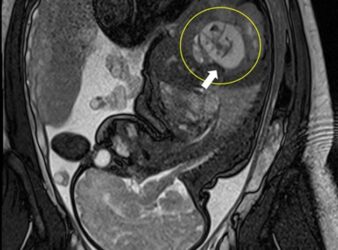

Amrita Hospital, Kochi Treats Rare Fetus-in-Fetu Case

KOCHI:Amrita Hospital, Kochi have successfully performed a rare and delicate surgery to remove a fetus.